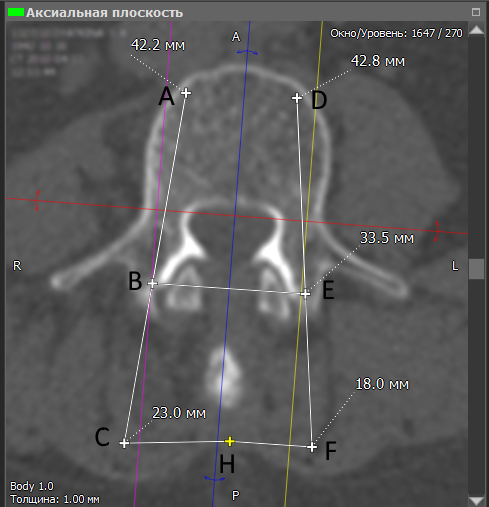

Далее пользователь прочерчивает на проблемном позвонке линии траектории введения винтов AC и DF. Точки B и E – это точки ввода винтов в позвонок, а получившиеся отрезки A-B и D-E определяют их будущее положение. Во всех плоскостях отображается проекция винтов, что позволяет дополнительно скорректировать траектории их введения, которые в одной плоскости могут быть оптимальными, но в других – оказаться нежелательными или даже опасными.

Определившись с положением обоих винтов, врач размечает на снимке точку H на остистом отростке, которая нужна для определения точек C и F. Программа автоматически определяет длины нужных отрезков, которые выводятся в миллиметрах. Зная точки введения винтов (B и E), а также нужные расстояния от остистого отростка (отрезки C-H и H-F), врач во время операции может определить траектории, по которым необходимо сверлить штифт-канал, чтобы установить винты в нужном положении.